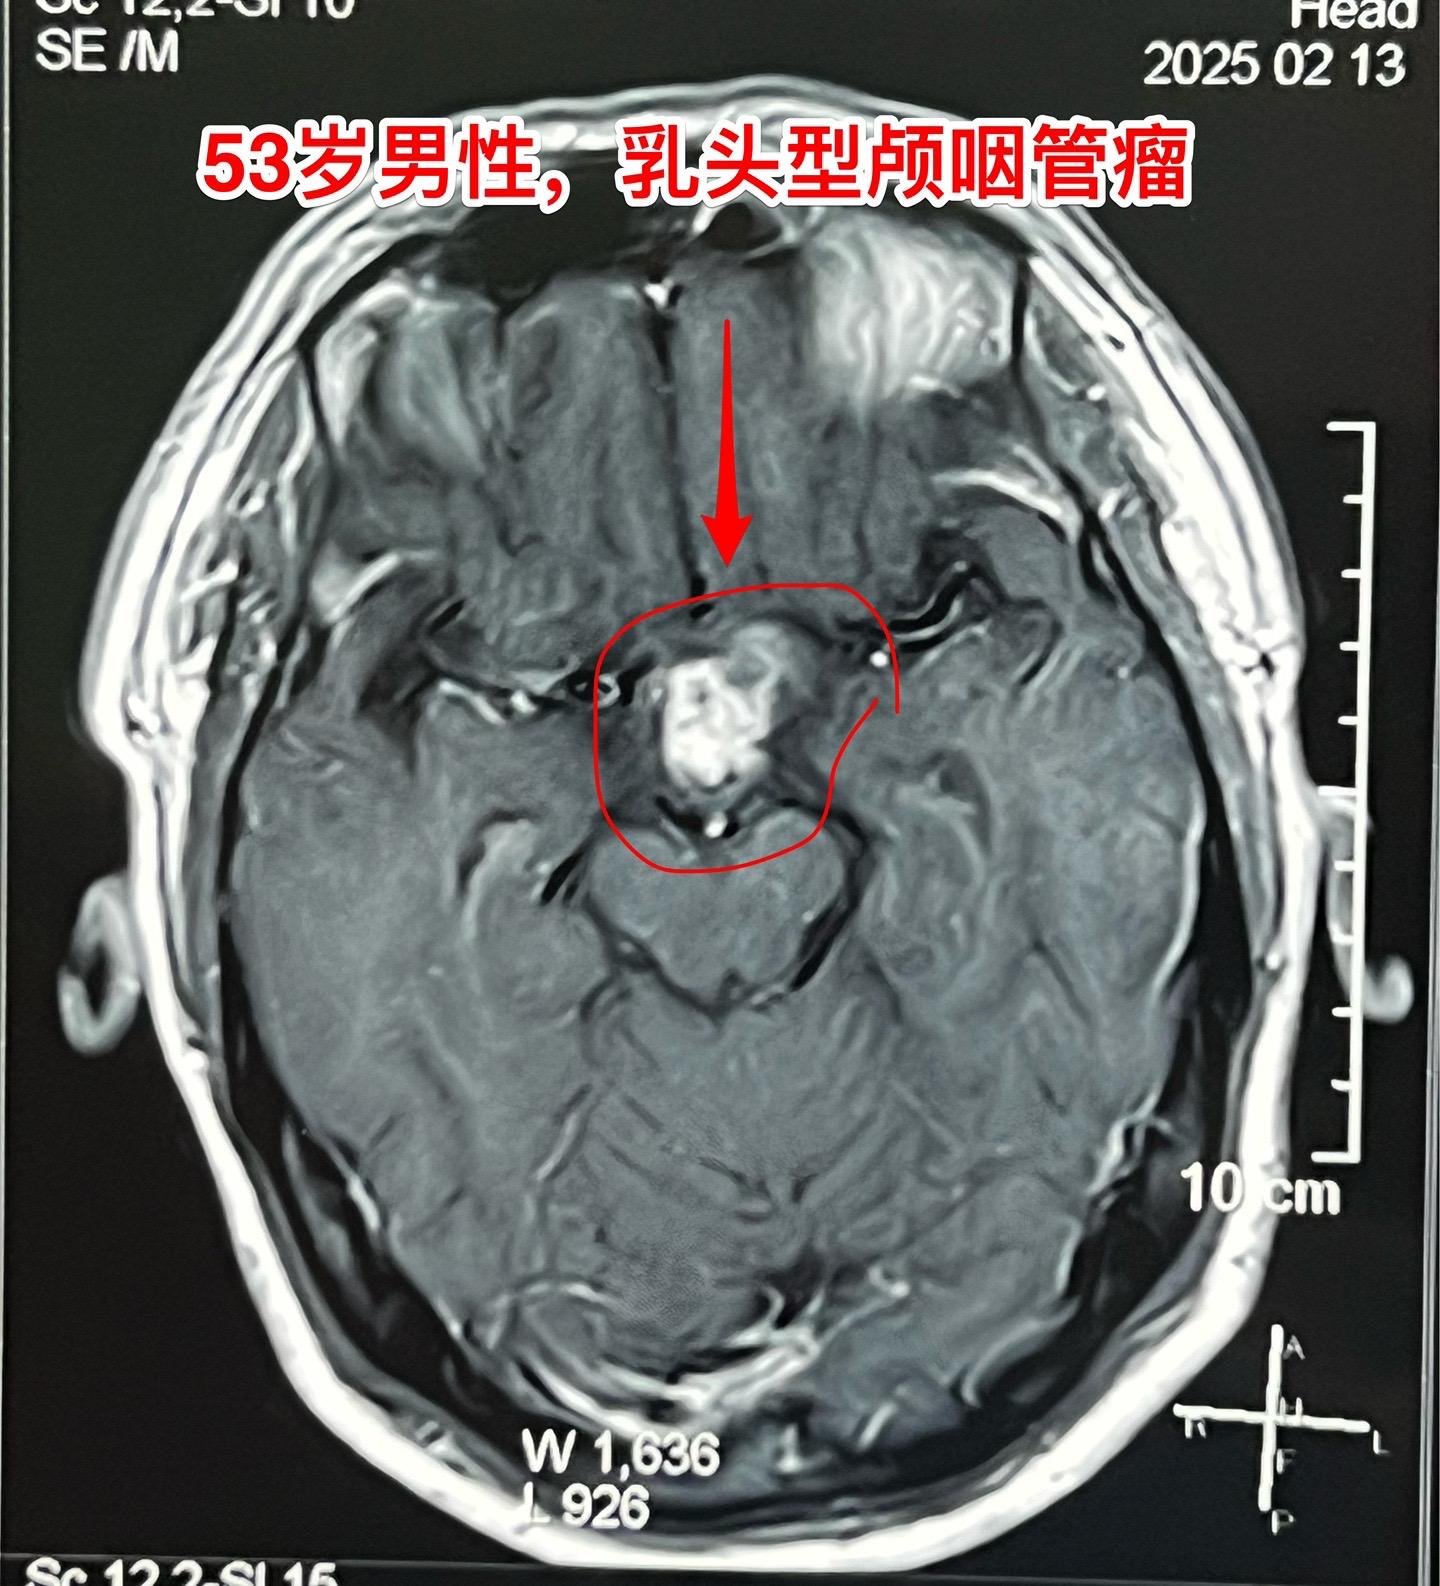

一天两个颅咽管瘤手术医生是很辛苦的 今天按计划作了两个颅咽管瘤手术。这是第二个病人,云南省文山州的警察,因记忆力差、爱睡觉、视力下降到医院检查发现了颅咽管瘤,是乳头型颅咽管瘤。 今天晚上九点多钟颅咽管瘤完全切除了,同时发现前交通动脉有个小动脉瘤,征得家人同意后作了动脉瘤夹闭术。期望病人一切都好!